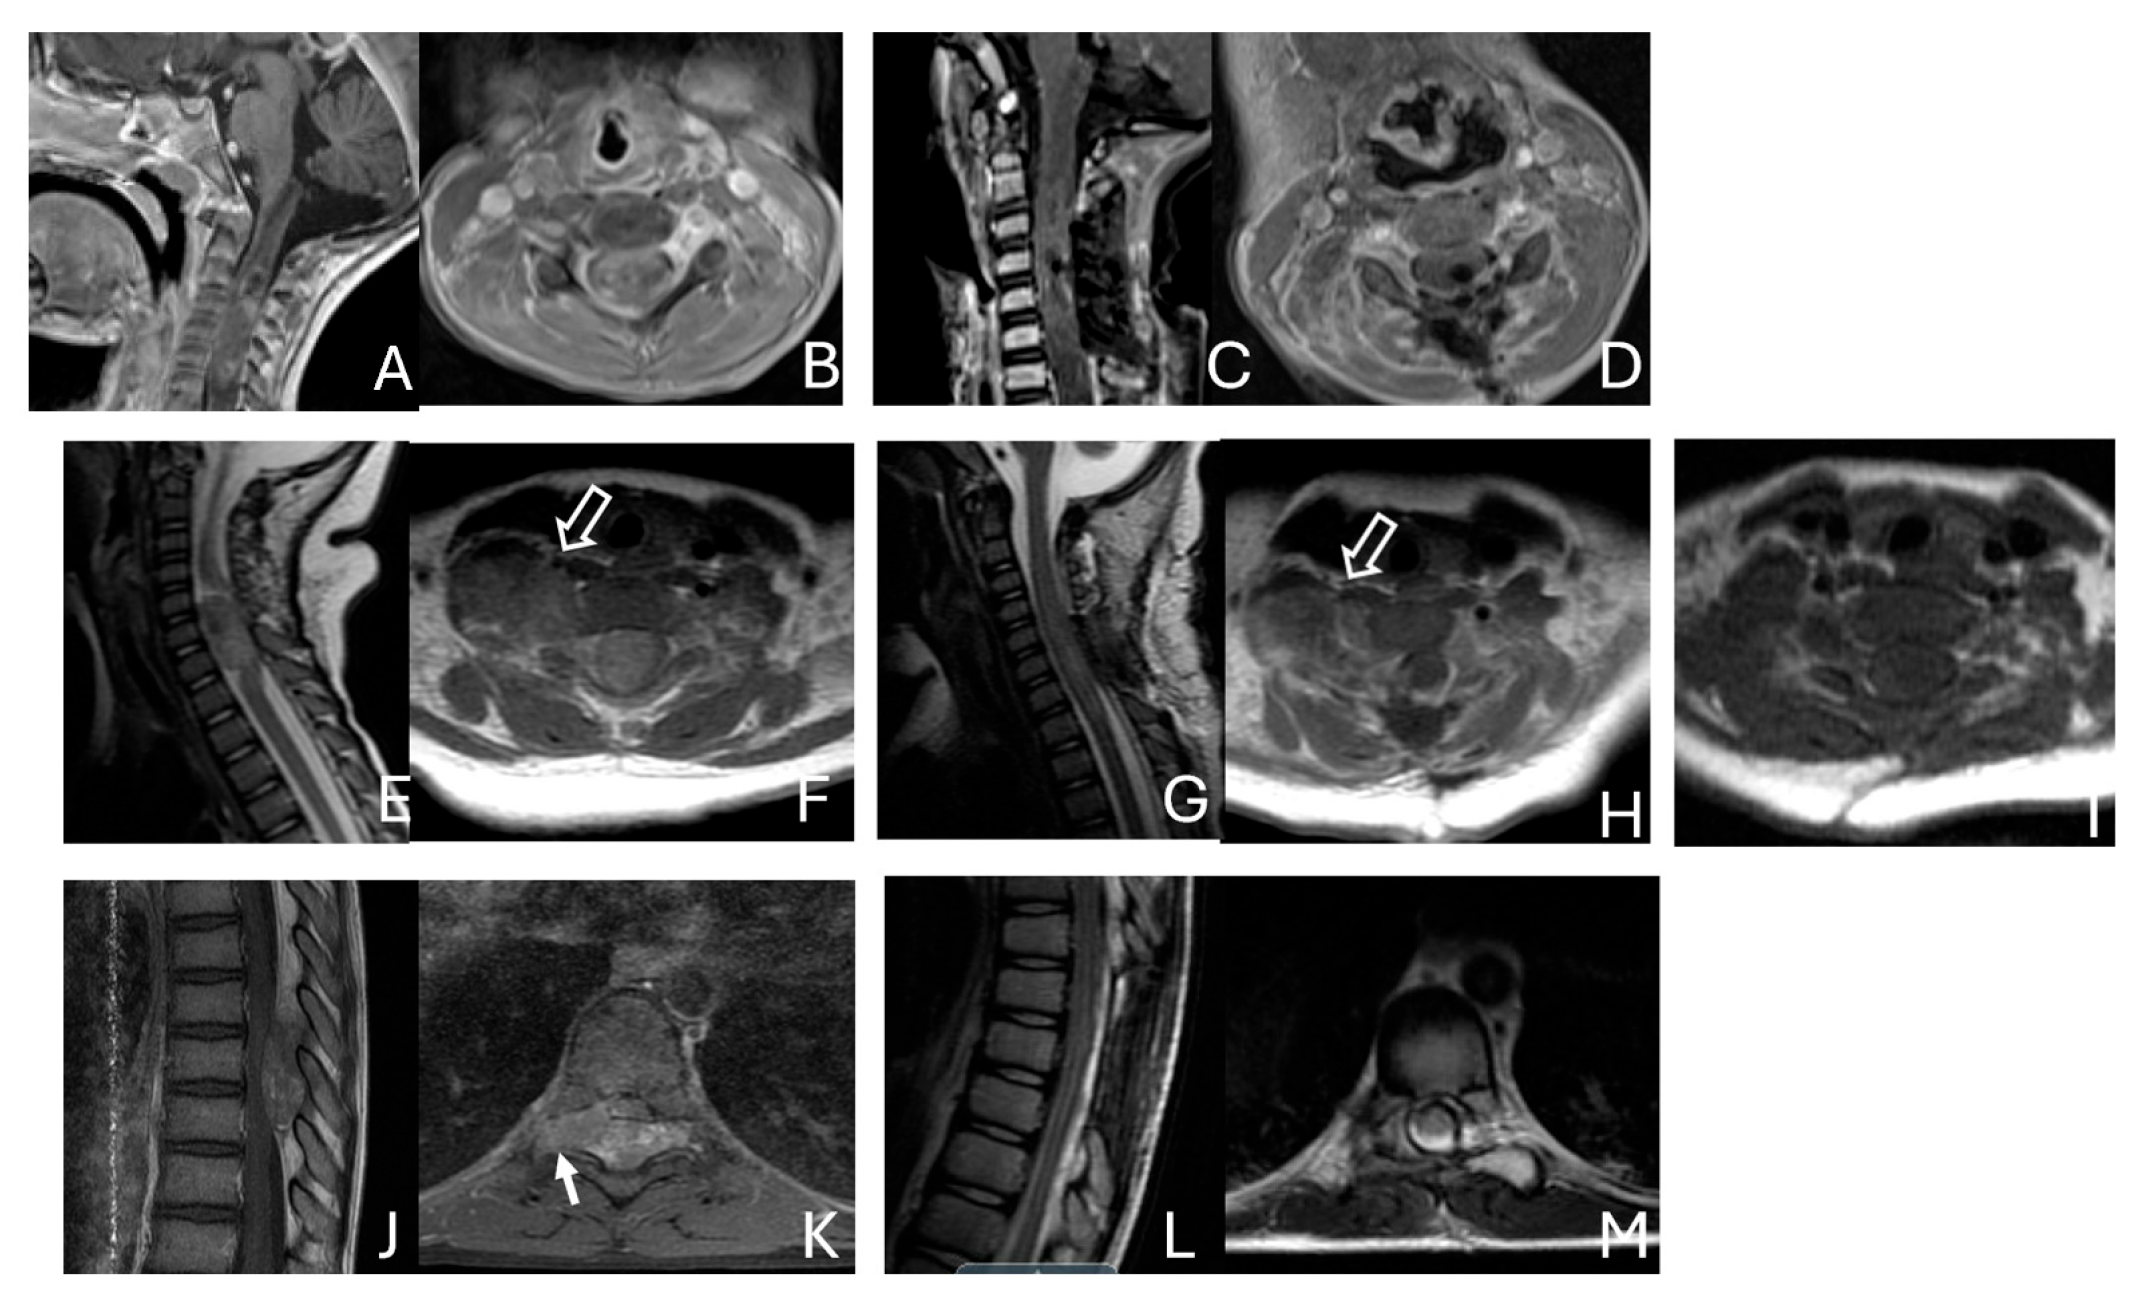

Figure 11.

Spine ATRT. (A–D): MR images ((A), sagittal; (B), axial) of a 34-month-old girl show a heterogeneous intramedullary cervical tumor centered at C3–C5. Postoperative images ((C), sagittal; (D), axial) demonstrate gross-total resection. (E–I): T2-weighted sagittal MR (E) and post-contrast axial MR (F) of a 7-month-old girl show a C5–C7 intradural–extramedullary ATRT with extradural and extraspinal extension (open arrow). The intradural–extramedullary component from the C6 dorsal nerve root and the epidural component into the neural foramina were resected (G), sagittal; (H), axial through a laminoplastic laminotomy, note a persistent paraspinal tumor (open arrow). Following chemotherapy, the residual paraspinal component was subsequently resected via an anterior cervical approach ((I), axial). (J–M): Mid-thoracic MR images ((J), sagittal; (K), axial) of a 9-year-old boy show a dorsal epidural ATRT from T7 to T9 with right-sided neural foraminal extension (arrow). An epidural ATRT was removed through laminectomy ((L), sagittal; (M), axial).

Another child, the oldest in this cohort, was an 11-year-old boy who presented with a dumbbell-shaped intradural extramedullary ATRT extending into the extradural space and neural foramina at the C5-T11 levels. Additionally, a 9-year-old boy had ATRT located in the epidural space, extending into the neural foramina at the T7–9 levels (Figure 11J–M).

Only one case involved an intramedullary tumor located in the cervical cord of a 34-month-old girl (Figure 11A–D). Two patients, a 64-month-old girl and a 96-month-old girl, had intradural extramedullary tumors situated at the T12-L1 and L3-S2 levels, respectively. Additionally, a 7-month-old girl presented with a contiguous intradural extramedullary and extradural tumor that extended outward to the paraspinal structures (Figure 11E–I). She underwent a staged operation, initially through a cervical laminoplastic laminotomy at the C5–7 level, followed by a second surgery via an anterior cervical approach for the total resection of the extraspinal disease after chemotherapy.